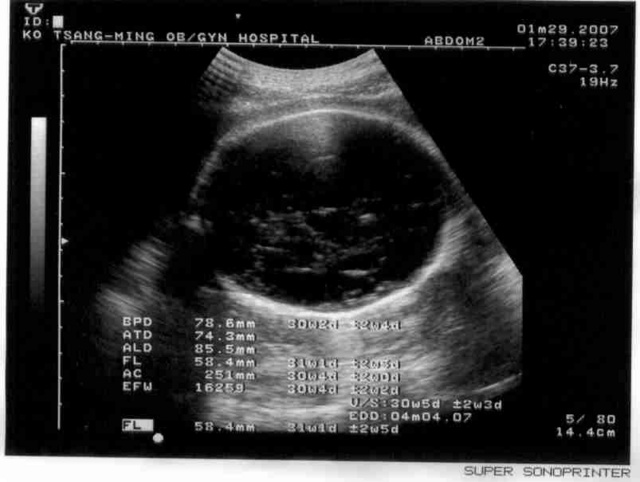

2007.01.29

從瑞士回來了,小寶寶很健康,準備要轉去台大醫院產檢和生產準備了,也是照臉,一切正常,1600g。